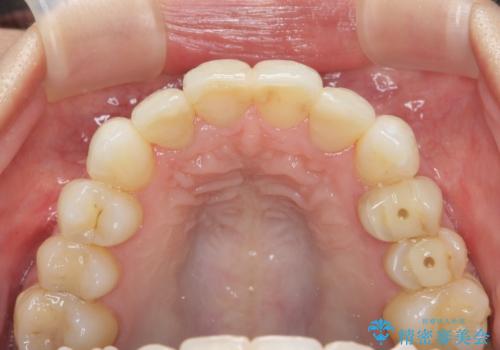

上顎4前歯は、根管治療の既往があり、虫歯も見られたことからブリッジによる治療で審美性の回復を行うとともに臨在歯の虫歯もセラミック治療を行っていきます。

欠損部の歯ぐきの量が足りない場合は、移植を行い歯肉を増大させることもありますが、今回は仮歯で様子を見た結清掃性・審美性に問題が出なかったので行いませんでした。